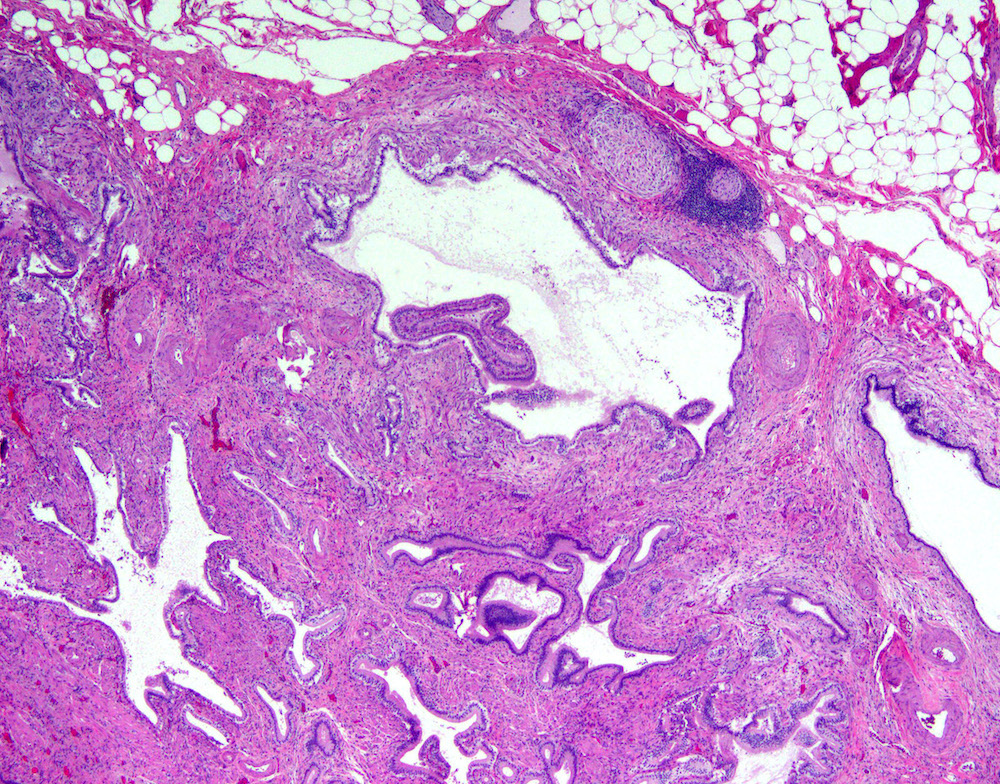

Microscopic (histologic) description

- Cystically dilated benign biliary glands accompanied by smooth muscle hypertrophy of gallbladder wall, thickened / fibrotic subserosa (StatPearls: Adenomyomatosis [Accessed 26 January 2021])

- Glands are distinct from the Rokitansky-Aschoff sinuses, which are epithelial diverticula, usually multifocal and occur throughout gallbladder secondary to injury, versus adenomyomatous nodule (distinct localized lesion of the gallbladder wall, 1 - 1.5 cm mural nodule in the fundus) (Am J Surg Pathol 2020;44:1649)

- May have reactive epithelial changes, papillary change and intestinal metaplasia (StatPearls: Adenomyomatosis [Accessed 26 January 2021])

- Rarely, benign glands are seen in proximity to nerves, appearing as perineural and intraneural invasion only in the subserosal layer (benign gland-like structures may migrate into nerves due to chemotactic factors or signaling substances with activation of cell receptors) (Am J Surg Pathol 2007;31:1598)

- Adenomyomatous nodules may rarely show dysplastic / carcinomatous transformation, whereas dysplasia in Rokitansky-Aschoff sinuses appears to be more common; however, the true association between adenomyomatous nodules and neoplasia has not yet been determined (Am J Surg Pathol 2020;44:1649)

- Recently, papillary dysplastic lesions of adenomyomas have been identified (intracholecystic neoplasms of adenomyomas), demonstrating cystic and solid areas with papillary projections that show biliary, gastric and intestinal phenotypes, with low or high grade dysplasia (Am J Surg Pathol 2020;44:1649)

Microscopic (histologic) images

Contributed by Monica T. Garcia-Buitrago, M.D.